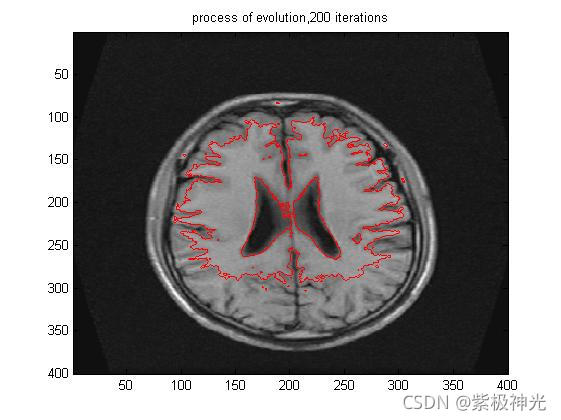

for k=1:numIter

u=EVOL_CV(Img, u, nu, lambda_1, lambda_2, timestep, epsilon, 1); % update level set function

if mod(k,10)==0

pause(.1);

imagesc(Img,[0 255]);colormap(gray)

hold on;

contour(u,[0 0],'r');

iterNum=[num2str(k), ' iterations'];

title(['process of evolution,',iterNum]);

hold off;

end

end;

四、运行结果